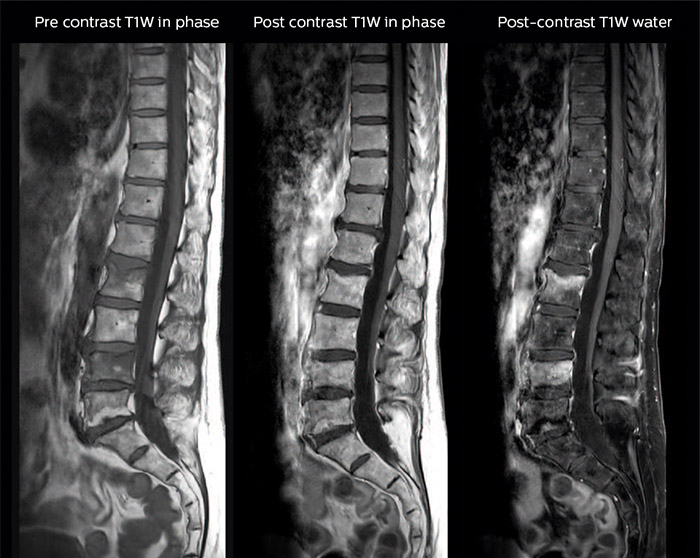

Spine scans must be fast and complete

“In our spine cases, we use mDIXON TSE for patients with degenerative and inflammatory spine issues, vertebral fractures and vertebral and paravertebral tumor characterization,” says Dr. Lefebvre. “It provides, in a single acquisition, different contrasts so we can both visualize and characterize spinal, focal or diffuse spine lesions.”

“mDIXON TSE makes real a difference in cases of acute and traumatic spinal injuries, where it allows us to reduce the scan time by only using a limited number of sequences. For patients in pain, who come from the emergency unit and need surgery, for example, MRI must be very fast. With a single T2-weighted acquisition we can assess spinal cord, vertebral disc and ligament wholeness with in-phase images, as well as trabecular fracture and edematous changes with water images.”

Dr. Lefebvre cites other frequent examples of spinal diseases that benefit from the mDIXON technique. “In cases of vertebral disc herniation or degenerative discs, for example, we don’t have to choose between fat or no fat images. We can assess morphological changes in the endplate with in-phase images from T2-weighted sequences and in the water image from the same acquisition we will see inflammatory changes into endplates.”